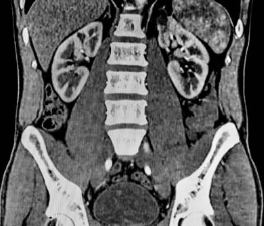

CT(Computed Tomography)는 X선을 사용하여 3차원 이미지를 생성하는 의료 영상 검사 기술 중 하나입니다. CT는 신체의 다양한 부위를 정확하게 촬영할 수 있어서 다양한 진단에 이용됩니다. 특히 뇌, 흉부, 복부 등의 내부 구조를 세밀하게 살펴볼 수 있어서 진단과 치료 계획에 큰 도움을 줍니다.

복부 CT는 복부 내부의 장기와 혈관, 림프절 등을 자세하게 촬영하여 그림으로 나타내는 영상진단 방법 중 하나입니다. 복부 CT를 통해 확인 가능한 질병은 매우 다양합니다.

복부 CT는 진단에 대한 정확성이 높고 비침습적인 방법으로 장기나 혈관의 구조나 기능상의 이상을 파악할 수 있어, 내과, 외과, 신경과, 영상의학과, 방사선종양학과 등 다양한 분야에서 활용되고 있습니다.